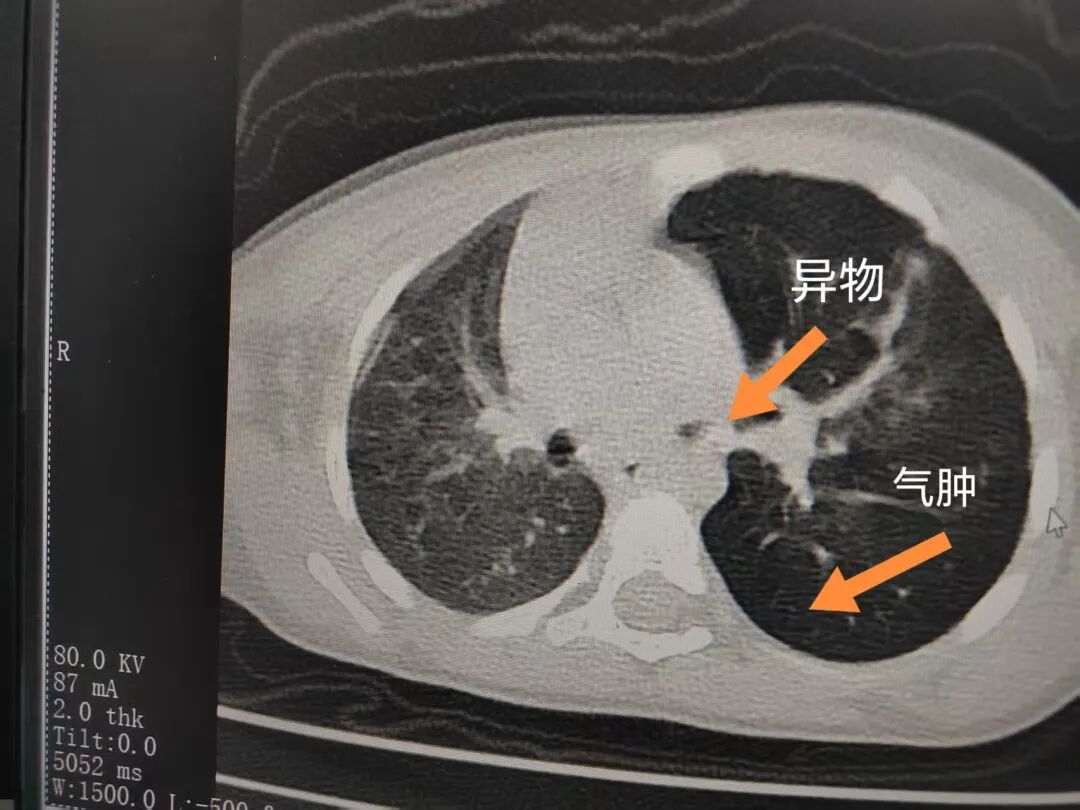

三天后(11月13日),趙寶出現(xiàn)高熱、咳喘加重,家長著急了,再次帶他來到醫(yī)院。CT檢查顯示左肺過度充氣,左肺上下葉支氣管主干見不規(guī)則高密度影,左肺上葉可見大片狀密度增高影,縱隔窗實(shí)變,提示為“左側(cè)支氣管內(nèi)異物并繼發(fā)性改變,左肺上葉舌段肺膨脹不全”。

市二院小兒呼吸內(nèi)科團(tuán)隊(duì)迅速為患兒制定了周密的手術(shù)方案,并很快安排了氣管鏡探查。術(shù)中,主治醫(yī)師田慧等憑借嫻熟的氣管鏡操作技術(shù)成功將異物大塊板栗取出。由于板栗在氣管內(nèi)存留時間較長,質(zhì)地軟糯易碎,大大增加了手術(shù)難度。檢查還發(fā)現(xiàn),異物停留部位的氣管黏膜已出現(xiàn)充血紅腫、糜爛,導(dǎo)致患兒住院時間相應(yīng)延長。此次事件給趙寶的家庭帶來了不小的驚嚇與擔(dān)憂,也再次為廣大家長敲響了警鐘。

市二院小兒呼吸內(nèi)科副主任楊亞娟介紹,異物誤入氣道可能導(dǎo)致氣道阻塞,嚴(yán)重時可引發(fā)窒息,甚至危及生命。若異物進(jìn)入支氣管,造成不完全堵塞,可引起阻塞性肺氣腫;如完全堵塞支氣管,則可能導(dǎo)致肺組織萎縮,形成肺不張。此外,若異物存留時間較長,或?yàn)橹参镄援愇铮菀缀喜⒓?xì)菌感染,產(chǎn)生膿性分泌物,進(jìn)而發(fā)展為肺炎。她強(qiáng)調(diào),盡早診斷并取出異物,是減少并發(fā)癥、降低病死率的關(guān)鍵。